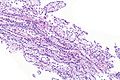

Prostatic-type polyp. H&E stain. (WC/Nephron) | |

| LM | benign prostatic type epithelium or transitional type epithelium +/-corpora amylacea |

| LM DDx | prostatic ductal carcinoma |

| IHC | PSA +ve |

| Site | urethra/prostate gland - verumontanum |

Prostatic-type polyp is an uncommon polyp of the genitourinary tract. It is typically centered on the verumontanum of the prostate gland and projects into the urethra.

Features:[2]

- Benign prostatic type epithelium or transitional type epithelium.

- Cuboidal to low columnar cells with basal cell layer.

- +/-Corpora amylacea.